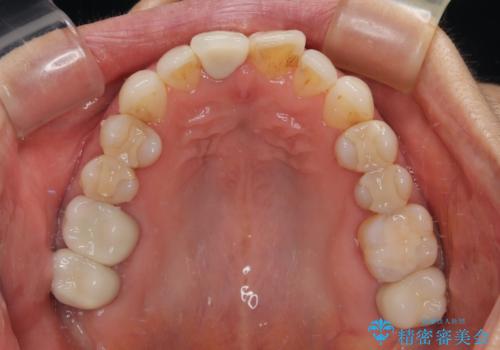

デコボコと銀歯 矯正治療とセラミック治療で綺麗な口元に

- 前歯のデコボコと口を開けたときに見える銀歯を気にして来院された患者様です。

ある程度デコボコが解消されれば大丈夫とのことで、インビザライン・モデレートパッケージを利用して歯列を整えて行くこととしました。

矯正治療後に銀歯をセラミッククラウンなどに置き換えていくと、どうしても後戻りを起こしてしまうため、矯正治療が概ね終了した時点で銀歯を全てセラミックとし、最後に仕上げでインビザラインにを用いて細かいデコボコを改善していくこととしました。

とても明るい口元となり、人目を気にせず、大きく口を開けて笑えるようになりました。